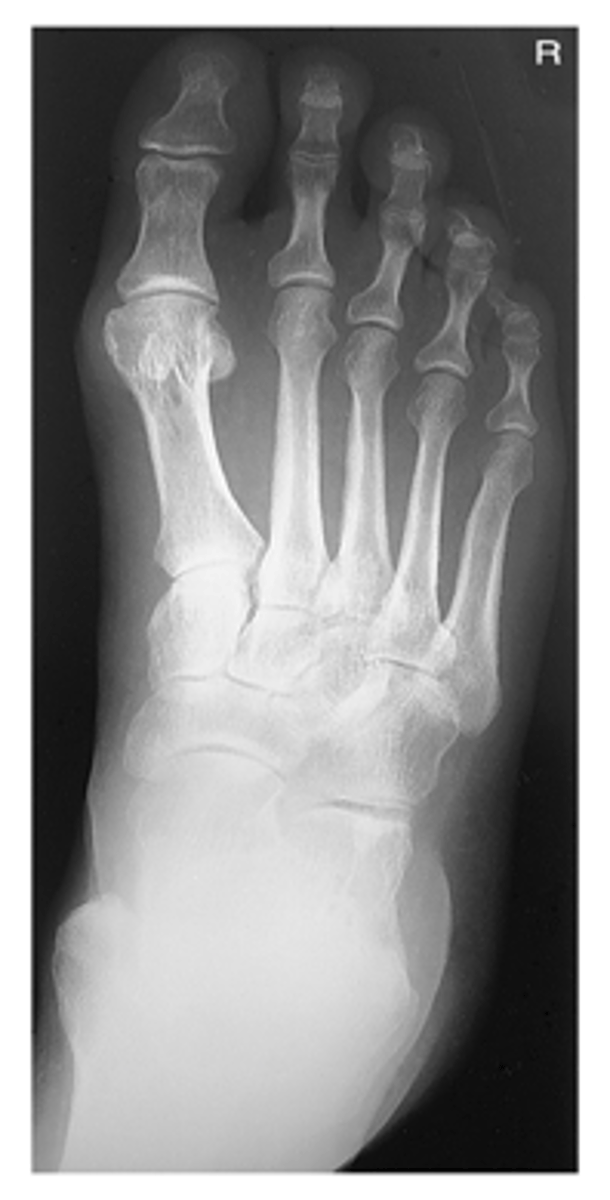

AP Foot

What projection is this?

Evaluation Criteria for AP Foot

- CR 10° angled posteriorly

- CR to base of 3rd MT

- Entire foot visualized

- No rotation of metatarsals

- MTP joints generally open

- Optimal exposure factors